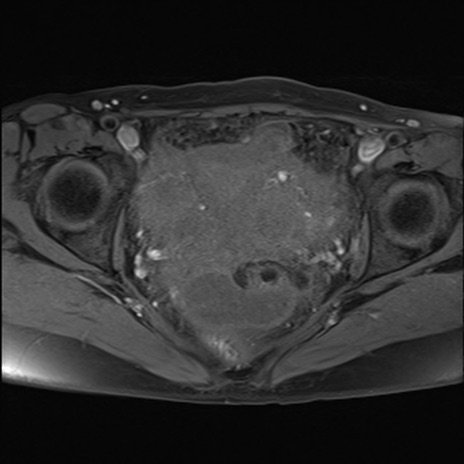

症例39 脂肪抑制T1WI(横断像)

MRI(4日後)

T2WI(横断像)